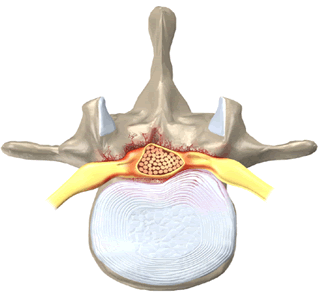

Оссификация ЗПС приводит к уменьшению передне-заднего диаметра спинномозгового канала, что приводит к стенозу спиннопозвоночного канала, сдавление спинного мозга.

Компьютерная томография (КТ).

- Характерный вид ЗПС в виде «перевернутой буквы Т» или «галстука-бабочки» на аксиальных срезах.

- Картина оссификации ЗПС аналогичная таковой на бескострастных КТ срезах.

- Кортикальная пластинка, ограничивающая центрально расположенное костномозговое пространство, может соединиться с подлежащей покровной пластинкой.

- Тела позвонка либо быть отграниченной от нее.

- Костномозговые пространства оссифицированной ЗПС и тела позвонка не сообщаются.